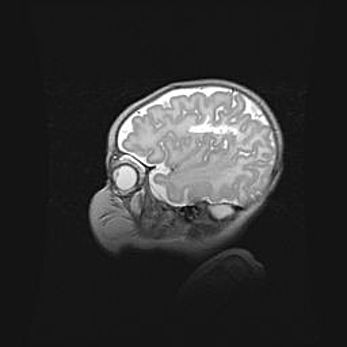

Церебральная ишемия II.

Возраст: 5 дней

Вес: 3400 г

Пол: женский

Окружность головы: 35 см

Срок гестации: 39 недель

Церебральная ишемия – это заболевание, характеризующееся недостаточностью (гипоксией) либо полным прекращением (аноксией) снабжения мозга кислородом по причине закупорки одного или нескольких сосудов. Это приводит к  что метаболическим расстройствам различной степени тяжести в тканях головного мозга, развитию коагуляционных некрозов и гибели нейронов.